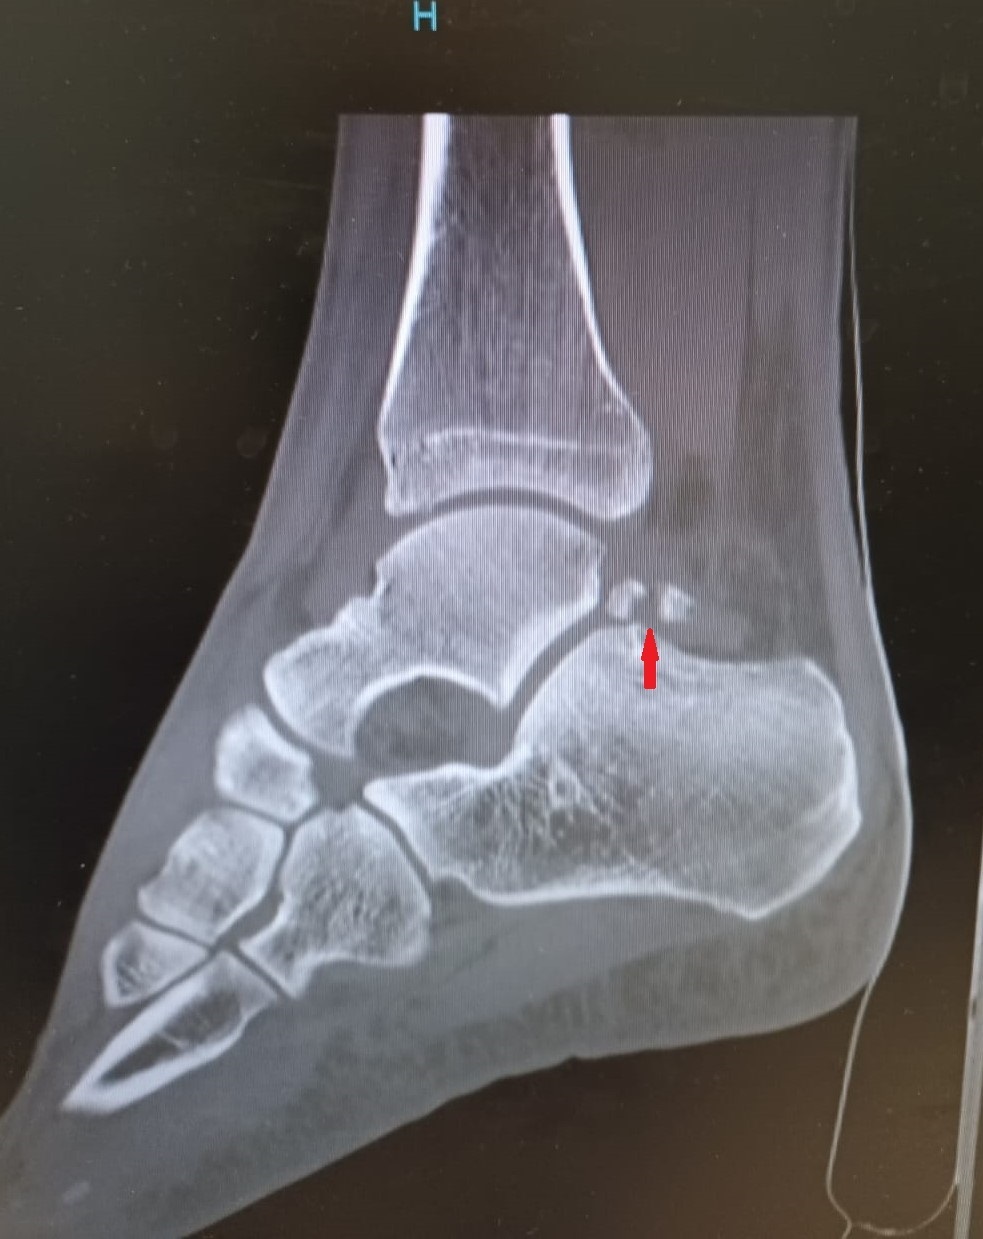

Miguel, 41 ans, consulte à la suite d’une chute mal réceptionnée dans le bassin d’un toboggan de parc aquatique. Depuis, il a une douleur avec impotence fonctionnelle du pied droit. À son arrivée au cabinet, il a une attitude antalgique avec claudication à droite. L’examen clinique révèle une douleur reproductible lors de la flexion plantaire et à la palpation du talon. Aucun trouble sensitif ni vasculaire n’est observé. Le mollet est souple et indolore, sans signe de Thompson. Un bilan radiographique est effectué, révélant la fracture d’un os trigone surnuméraire (fig. 1, flèche).

Le diagnostic est souvent difficile, et les fractures non déplacées sont généralement confondues avec une entorse de la cheville, une tendinite péronière ou une tendinite d’Achille. Une radiographie normale n’exclut pas la pathologie ;1,3 un scanner ou une IRM est souvent nécessaire. Cette fracture se distingue des fractures de Cedell et de Cloquet-Shepherd, qui affectent les tubercules postérieurs du talus.4